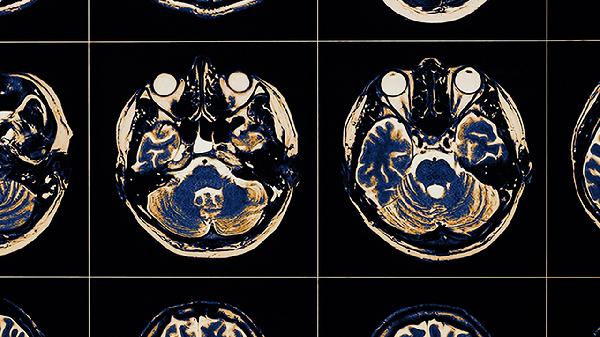

老年人大脑萎缩的后期症状主要有记忆力严重减退、定向力障碍、语言功能丧失、行为异常、生活完全不能自理等。大脑萎缩是一种进行性神经退行性改变,后期症状往往提示疾病已进入终末阶段。

患者会出现时间、地点、人物定向力完全丧失,可能在家中迷路,将白天误认为黑夜。这与大脑顶叶和额叶功能受损相关。家属需保持家居环境固定不变,避免频繁更换物品位置。医生可能通过脑电图和头部MRI评估病变范围。